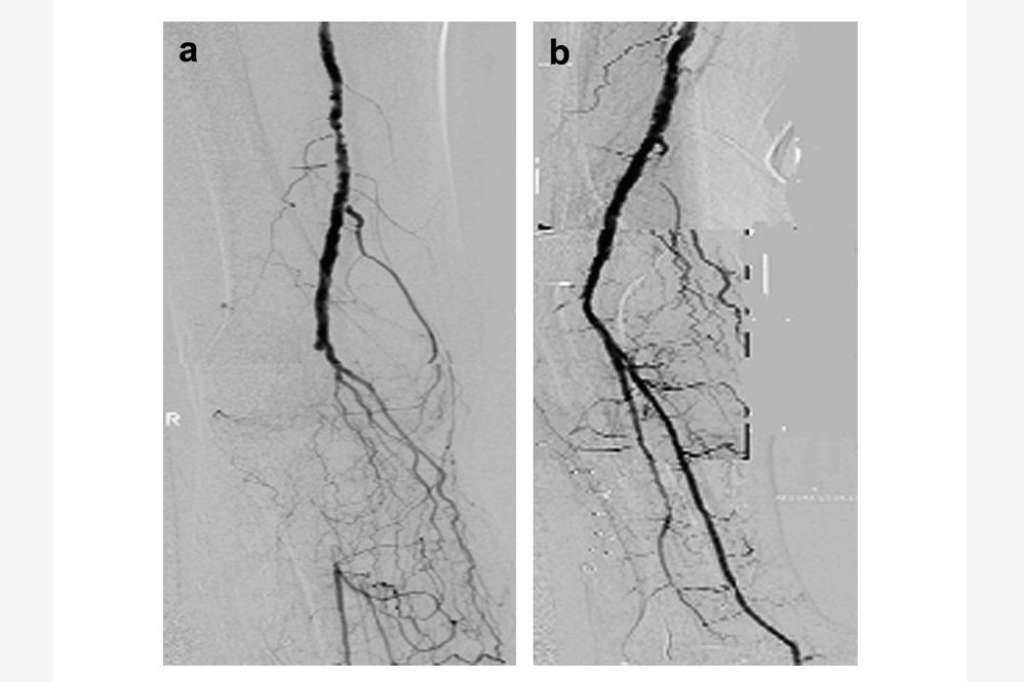

SARAJEVO, 16. januara (FENA) - Periferna arterijska bolest (PAD) je hronična, progresivna aterosklerotska bolest koja najčešće zahvata arterije donjih ekstremiteta, smanjujući protok krvi i dovodeći do ishemije tkiva. Zbog smanjenog protoka krvi, tkiva ne dobivaju dovoljno kisika i hranljivih tvari što značajno narušava kvalitet života a može dovesti i do brojnih komplikacija.